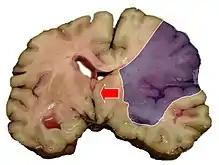

Midline shift (arrow) is present in this brain after a stroke (infarct depicted in shaded area).

Midline shift is a shift of the brain past its center line.[1] The sign may be evident on neuroimaging such as CT scanning.[1] The sign is considered ominous because it is commonly associated with a distortion of the brain stem that can cause serious dysfunction evidenced by abnormal posturing and failure of the pupils to constrict in response to light.[1] Midline shift is often associated with high intracranial pressure (ICP), which can be deadly.[1] In fact, midline shift is a measure of ICP; presence of the former is an indication of the latter.[2] Presence of midline shift is an indication for neurosurgeons to take measures to monitor and control ICP.[1] Immediate surgery may be indicated when there is a midline shift of over 5 mm.[3][4] The sign can be caused by conditions including traumatic brain injury,[1] stroke, hematoma, or birth deformity that leads to a raised intracranial pressure.